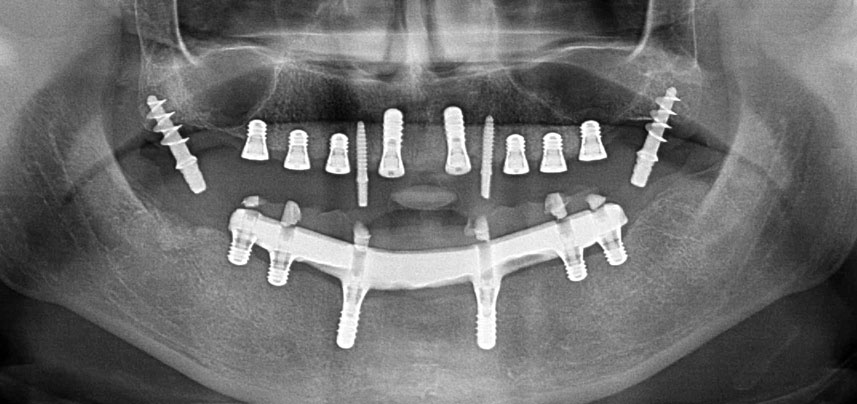

Три години по-късно е дошло времето за максиларна протеза от същия тип. Въз основа на планирането със CBCT, аугментацията на синусите е избегната с помощта на къси импланти и използването на хирургичен шаблон, за да се прехвърлят планираните позиции в алвеоларния гребен. (Фиг. 1 и 2).

Поради сравнително твърдата кост (D2) в тази област, 10-милиметровото имплантно ложе в позиции 11 и 21 беше завършено с ротационен дрил с диаметър 4 mm в комбинация с W&H хирургичен обратен наконечник WS-75 L, W&H имплантологичен мотор Implantmed и опционалния W&H Osstell ISQ модул. За разлика от това, благодарение на меката кост, дисталните зони се подготвят до окончателен диаметър 3 mm, използвайки накрайник за Piezomed I3P. Имплантите най-накрая са поставени трансгингивално, за да остеоинтегрират за три месеца (Фиг. 6-10). Съществуващата протеза се фиксира на четирите временни импланта (Фиг. 8).